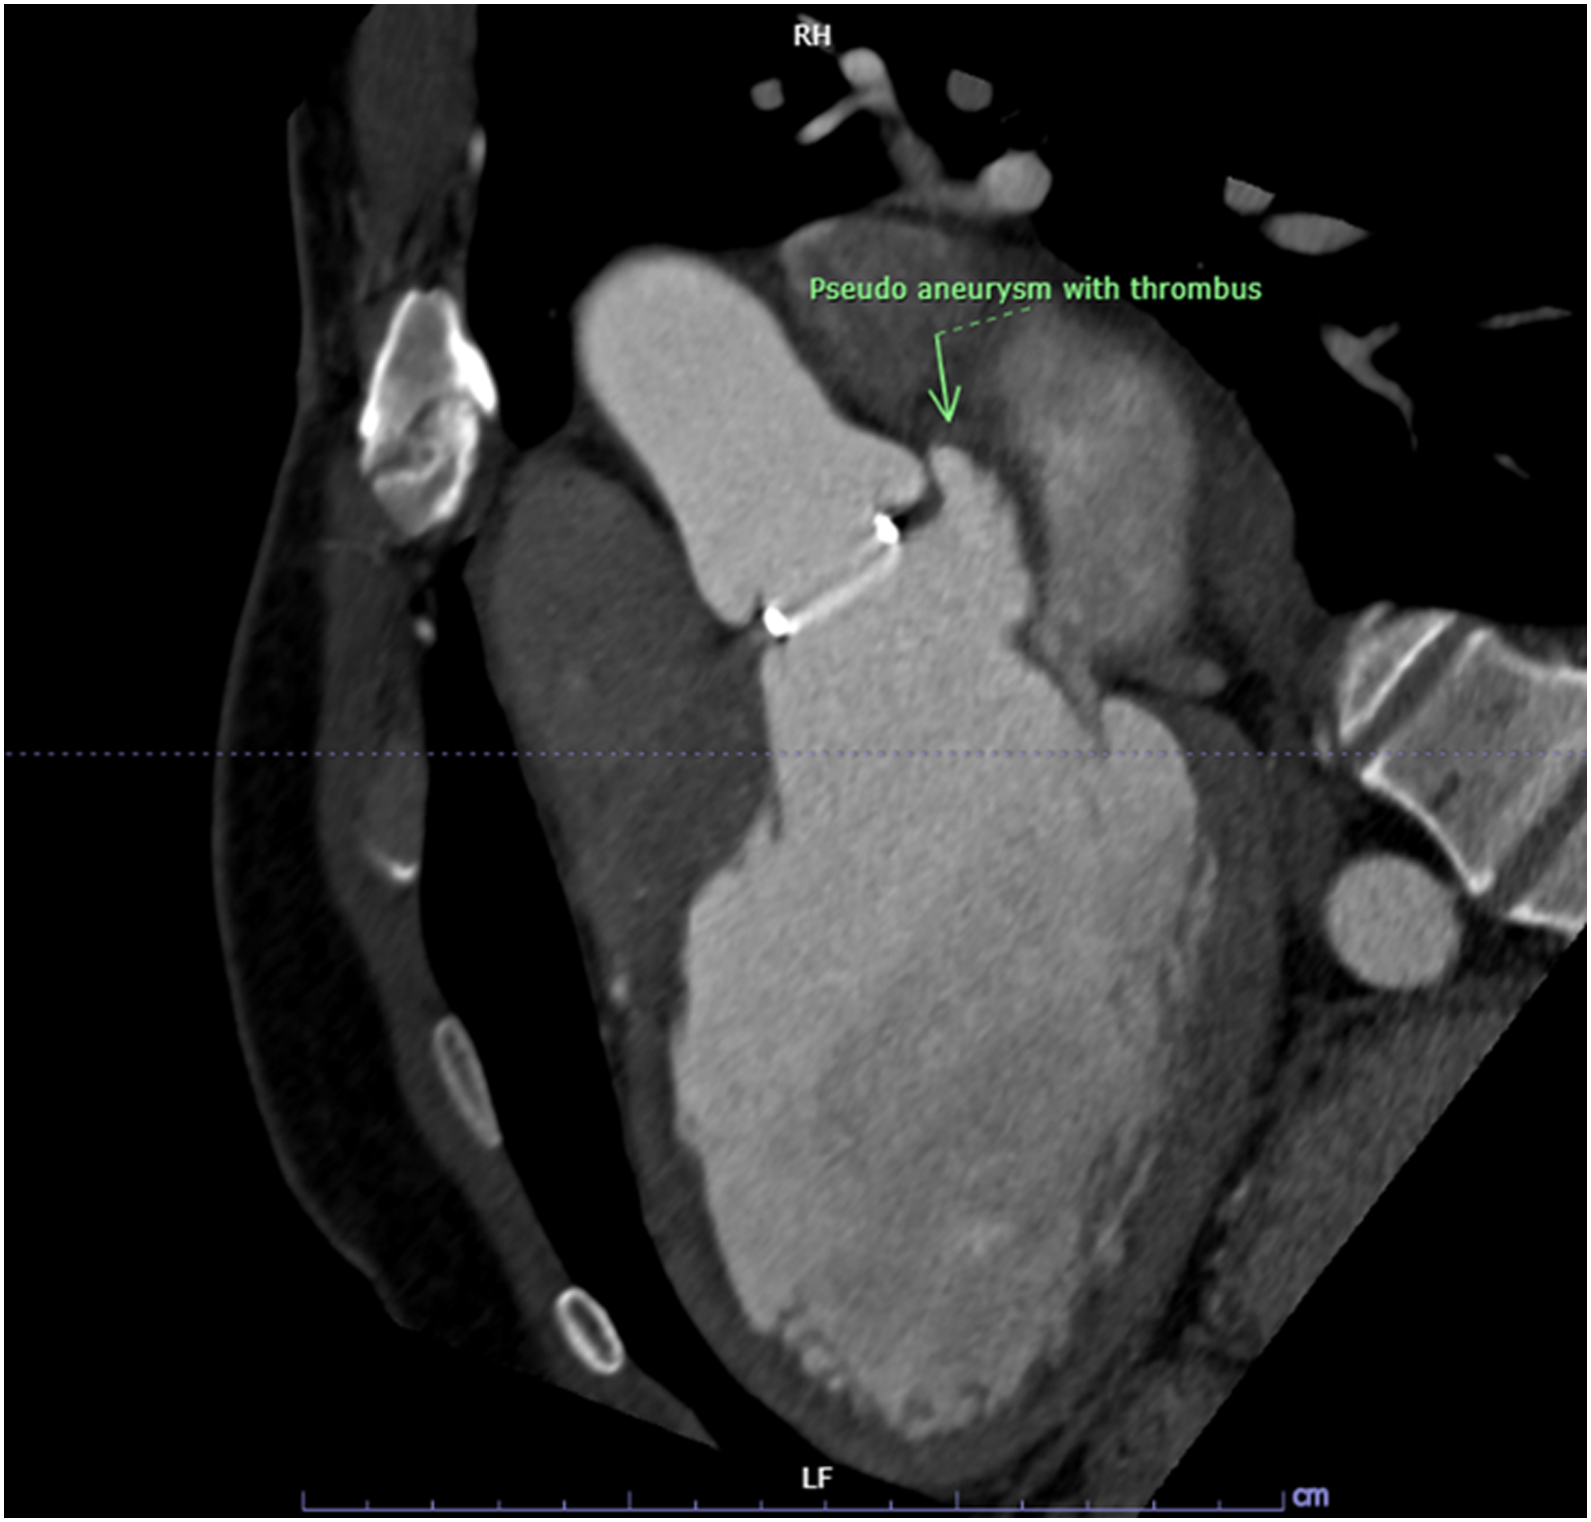

CT cardiac revealed pseudoaneurysm of the aortomitral intervalvular fibrosa with laminated thrombus with no LAA thrombus visualized.